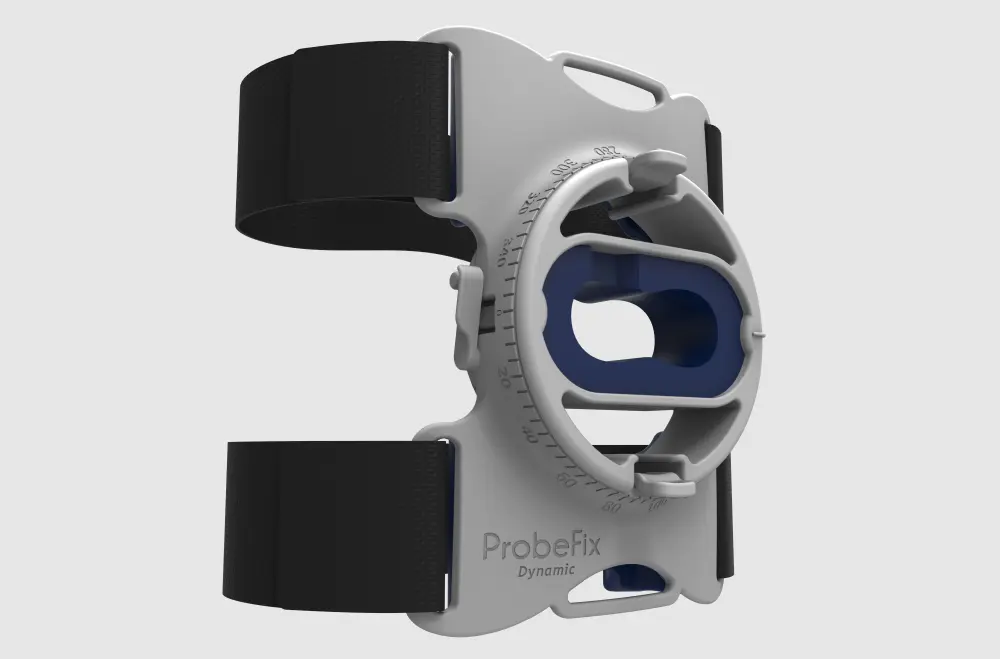

ProbeFix Dynamic is a new device that enables high-quality ultrasound measurements during dynamic exercise by keeping an ultrasound probe in place, allowing for muscle monitoring during intense movement and creating new research possibilities in muscle imaging.